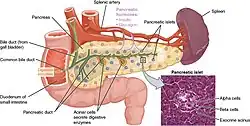

The pancreas is an organ that in humans lies in the abdomen, stretching from behind the stomach to the left upper abdomen near the spleen. In adults, it is about 12–15 centimetres (4.7–5.9 in) long, lobulated, and salmon-coloured in appearance.[7]

Anatomically, the pancreas is divided into a head, neck, body, and tail. The pancreas stretches from the inner curvature of the duodenum, where the head surrounds two blood vessels: the superior mesenteric artery and vein. The longest part of the pancreas, the body, stretches across behind the stomach, and the tail of the pancreas ends adjacent to the spleen.[7]

Two ducts, the main pancreatic duct and a smaller accessory pancreatic duct run through the body of the pancreas. The main pancreatic duct joins with the common bile duct forming a small ballooning called the ampulla of Vater (hepatopancreatic ampulla). This ampulla is surrounded by a muscle, the sphincter of Oddi. This ampulla opens into the descending part of the duodenum. The opening of the common bile duct into main pancreatic duct is controlled by sphincter of Boyden. The accessory pancreatic duct opens into duodenum with separate openings located above the opening of the main pancreatic duct.[7]

The head of the pancreas sits within the curvature of the duodenum, and wraps around the superior mesenteric artery and vein. To the right sits the descending part of the duodenum, and between these travel the superior and inferior pancreaticoduodenal arteries. Behind rest the inferior vena cava, and the common bile duct. In front sit the peritoneal membrane and the transverse colon.[7] A small uncinate process emerges from below the head, situated behind the superior mesenteric vein and sometimes artery.[7]

The neck of the pancreas separates the head of the pancreas, located in the curvature of the duodenum, from the body. The neck is about 2 cm (0.79 in) wide, and sits in front of where the portal vein is formed. The neck lies mostly behind the pylorus of the stomach, and is covered with peritoneum. The anterior superior pancreaticoduodenal artery travels in front of the neck of the pancreas.[7]

The body is the largest part of the pancreas, and mostly lies behind the stomach, tapering along its length. The peritoneum sits on top of the body of the pancreas, and the transverse colon in front of the peritoneum.[7] Behind the pancreas are several blood vessels, including the aorta, the splenic vein, and the left renal vein, as well as the beginning of the superior mesenteric artery.[7] Below the body of the pancreas sits some of the small intestine, specifically the last part of the duodenum and the jejunum to which it connects, as well as the suspensory ligament of the duodenum which falls between these two. In front of the pancreas sits the transverse colon.[8]

The pancreas narrows towards the tail, which sits near to the spleen.[7] It is usually between 1.3–3.5 cm (0.51–1.38 in) long, and sits between the layers of the ligament between the spleen and the left kidney. The splenic artery and vein, which also passes behind the body of the pancreas, pass behind the tail of the pancreas.[7]

Blood supply

The pancreas has a rich blood supply, with vessels originating as branches of both the coeliac artery and superior mesenteric artery.[7] The splenic artery, the largest branch of the celiac trunk, runs along the top of the pancreas, and supplies the left part of the body and the tail of the pancreas through its pancreatic branches, the largest of which is called the greater pancreatic artery.[7] The superior and inferior pancreaticoduodenal arteries run along the back and front surfaces of the head of the pancreas adjacent to the duodenum. These supply the head of the pancreas. These vessels join together (anastamose) in the middle.[7]

The body and neck of the pancreas drain into the splenic vein, which sits behind the pancreas.[7] The head drains into, and wraps around, the superior mesenteric and portal veins, via the pancreaticoduodenal veins.[7]

The pancreas contains tissue with an endocrine and exocrine role, and this division is also visible when the pancreas is viewed under a microscope.[10]

The majority of pancreatic tissue has a digestive role. The cells with this role form clusters (acini) around small ducts, and are arranged in lobes that have thin fibrous walls. The cells of each acinus secrete inactive digestive enzymes called zymogens into the small intercalated ducts which they surround. In each acinus, the cells are pyramid-shaped and situated around the intercalated ducts, with the nuclei resting on the basement membrane, a large endoplasmic reticulum, and a number of zymogen granules visible within the cytoplasm. The intercalated ducts drain into larger intralobular ducts within the lobule, and finally interlobular ducts. The ducts are lined by a single layer of column-shaped cells. There is more than one layer of cells as the diameter of the ducts increases.[10]

The tissues with an endocrine role within the pancreas exist as clusters of cells called pancreatic islets (also called islets of Langerhans) that are distributed throughout the pancreas.[9] Pancreatic islets contain alpha cells, beta cells, and delta cells, each of which releases a different hormone. These cells have characteristic positions, with alpha cells (secreting glucagon) tending to be situated around the periphery of the islet, and beta cells (secreting insulin) more numerous and found throughout the islet.[9] Enterochromaffin cells are also scattered throughout the islets.[9] Islets are composed of up to 3,000 secretory cells, and contain several small arterioles to receive blood, and venules that allow the hormones secreted by the cells to enter the systemic circulation.[9]